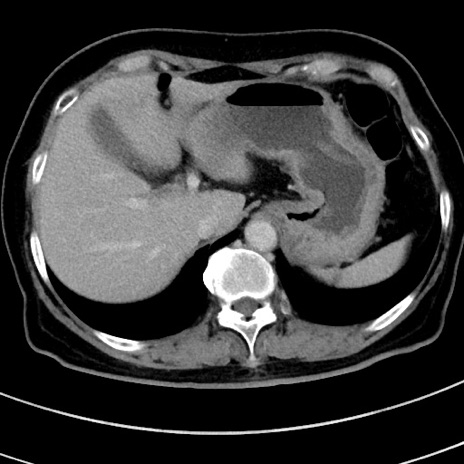

症例9(横断像)

【症例】 60歳代女性

【主訴】むかつき、みぞおちの痛み

【現病歴】3日前よりむかつきがあり、食事がとれない。

【既往歴】糖尿病

【身体所見】発熱なし、心窩部圧痛軽度あるも、腹膜刺激症状なし。

【データ】WBC 7400、CRP 1.92